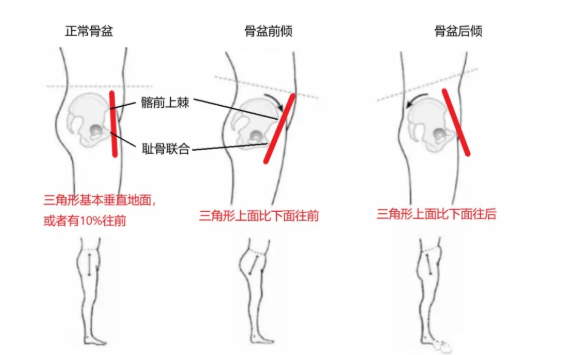

· 骨盆前倾 & 后倾:往往与腰椎过曲 & 过直同时发生,自我评估时可以通过观察腰部的曲度是否过大或过小来判断是否骨盆前倾或后倾。如果要更精确地评估,可以通过观察髂前上棘 (就是用手触摸骨盆最前沿的位置) 和耻骨 联合 (即 会阴 处)是否在一条铅垂线来判断,髂前上棘过于靠前则为骨盆前倾,过于靠后即为骨盆后倾。

1. 如果腰部与墙面的空隙可以插进一个手掌厚度,那是正常骨盆。

2. 如果能插进一个拳头,很可能骨盆前倾。

3. 如果基本插不进去,很可能是骨盆后倾。